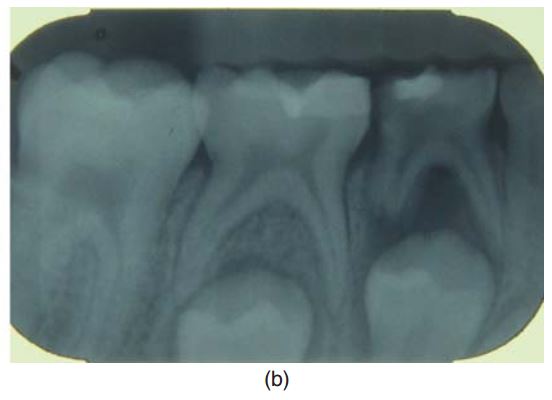

Nên chụp một phim quanh chóp trước điều trị để loại trừ nhiễm trùng, nội ngoại tiêu chân răng, đánh giá mức độ phát triển của chân răng (H6.2a).

Chân răng sữa thường rất mảnh, nếu có nội ngoại tiêu chân răng thì nên chỉ định nhổ (H6.2 b).